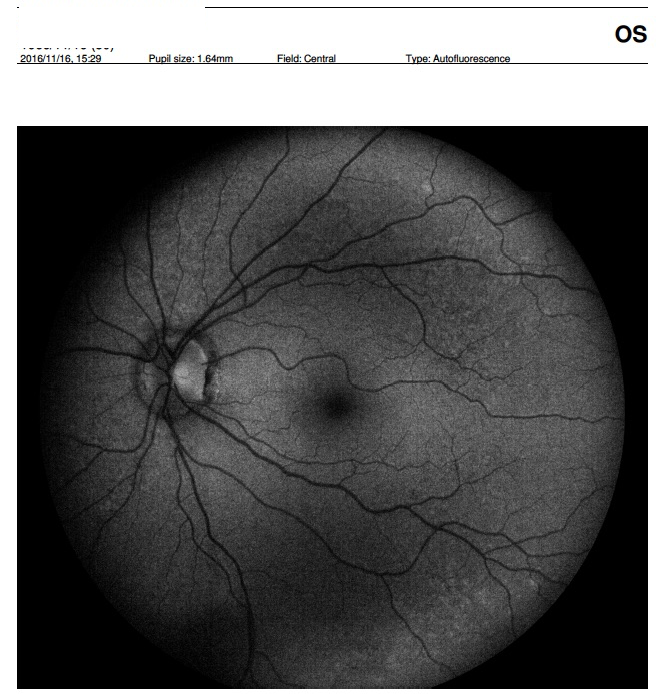

2) Autofluorescence with small pupil : 1.64mm